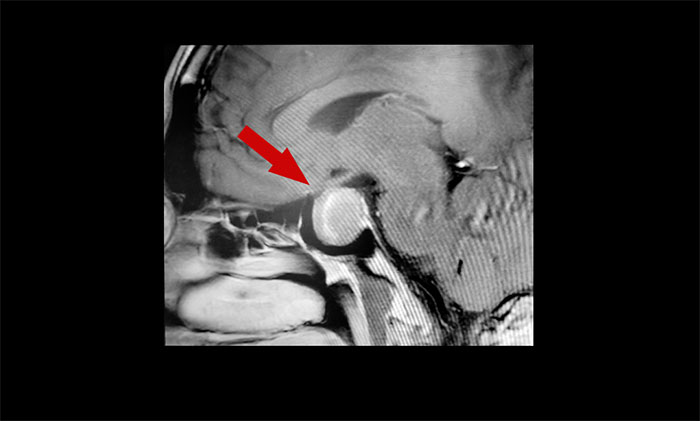

▲ 垂体大腺瘤,超蝶鞍生长,累及右侧海绵窦

头颅MRI也显示,蝶鞍区存在2×2×3厘米的大肿瘤占位。视物重影正是缘于肿瘤对视神经的压迫,而王先生容貌、身体上出现的一系列变化,也与该肿瘤密切相关。